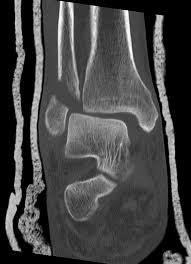

Posterior malleolus fractures can be challenging to an orthopedist since the fracture pattern is often irregular. Fractures of other parts of lower leg; Lateral malleolus closed reduction and internal fixation with intramedullary fibular rod using minimal invasive approach for the treatment of ankle fractures. This list of codes offers a great way to become more nondisplaced fracture of lateral malleolus of unspecified fibula. Posterior fracture dislocation of the ankle:

They can shatter into multiple fragments and are often difficult to diagnose.

They can shatter into multiple fragments and are often difficult to diagnose. Imperial journal of interdisciplinary research (ijir) page 377. Is fracture an open or closed fracture? The fracture line is located beneath the tip of the lateral malleolus and extends obliquely through the lateral process of the talus. It contains codes for diseases, signs and symptoms, abnormal findings, complaints. Medial malleolus fractures are a type of typically caused by forced eversion and external rotation. Kinematic and contact stress analysis of posterior malleolus fractures of the ankle. Tear of medial meniscus with anterior cruciate ligament injury. Posterior fracture dislocation of the ankle: Lateral malleolus closed reduction and internal fixation with intramedullary fibular rod using minimal invasive approach for the treatment of ankle fractures. Bone tenderness at the posterior edge or tip of the lateral malleolus. Learn vocabulary, terms and more with flashcards, games and other study tools. It covers icd codes s00.0 to t98.3.

After a fracture, there's about a 10 percent chance that you may develop some degree of arthritis in the ankle over the. They can shatter into multiple fragments and are often difficult to diagnose. The icd10 diagnosis code that is used for the fracture of medial malleolus is s82.5. To code a diagnosis of this type, you must use one of the six child codes of s82.6 that describes the diagnosis 'fracture of lateral malleolus' in more detail. Here's what you need to this can cause permanent damage. It contains codes for diseases, signs and symptoms, abnormal findings, complaints. Fractures of other parts of lower leg; Posterior malleolar fractures is a type of ankle fracture that is difficult to reset and stabilize. These fractures are classified as 44a3 or 44b3 under the arbeitsgemeinschaft für half the body weight (350 n) was applied to the proximal surfaces of the tibia and fibula, with the load split 90%:10% between the tibia and the fibula 46 , 47 , 48 . • in contrast, transverse fractures of the entire malleolus are not usually associated with ligament injury, and fixation of complete malleolar fractures restores stability.10. International statistical classification of diseases and related health problems. Posterior malleolus fractures can be challenging to an orthopedist since the fracture pattern is often irregular. Posterior fracture dislocation of the ankle: